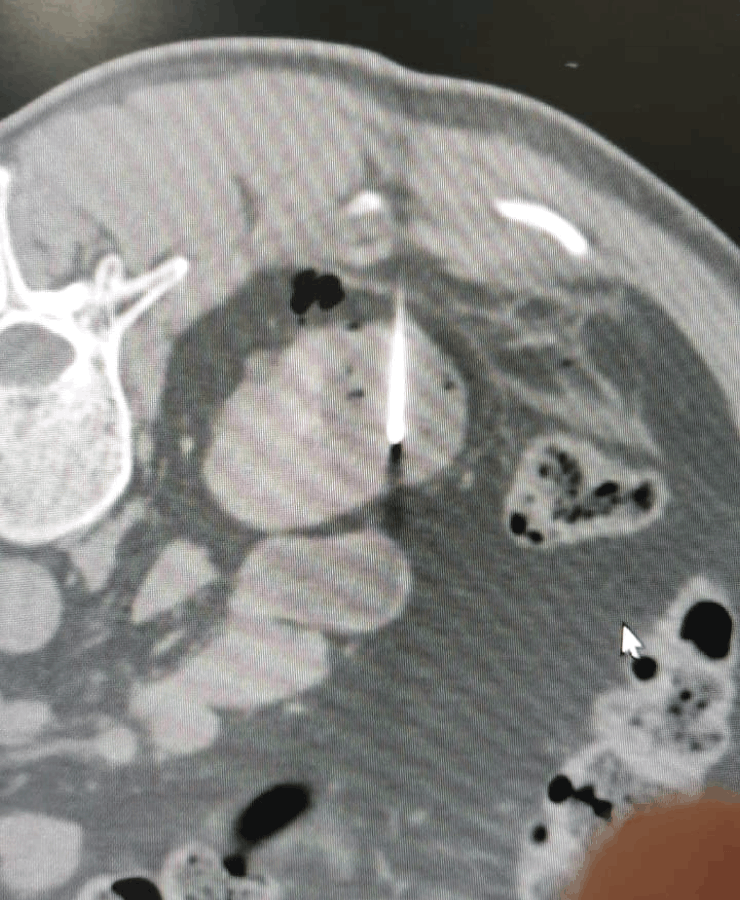

Insertion of microwave needle treatment of cancer

- Thermal ablation (radiofrequency or microwave): destroys tumour tissue by heating it from within through a thin needle placed under USG/CT guidance.

Kidney cancer treatment by Microwave Ablation method

Post treatment